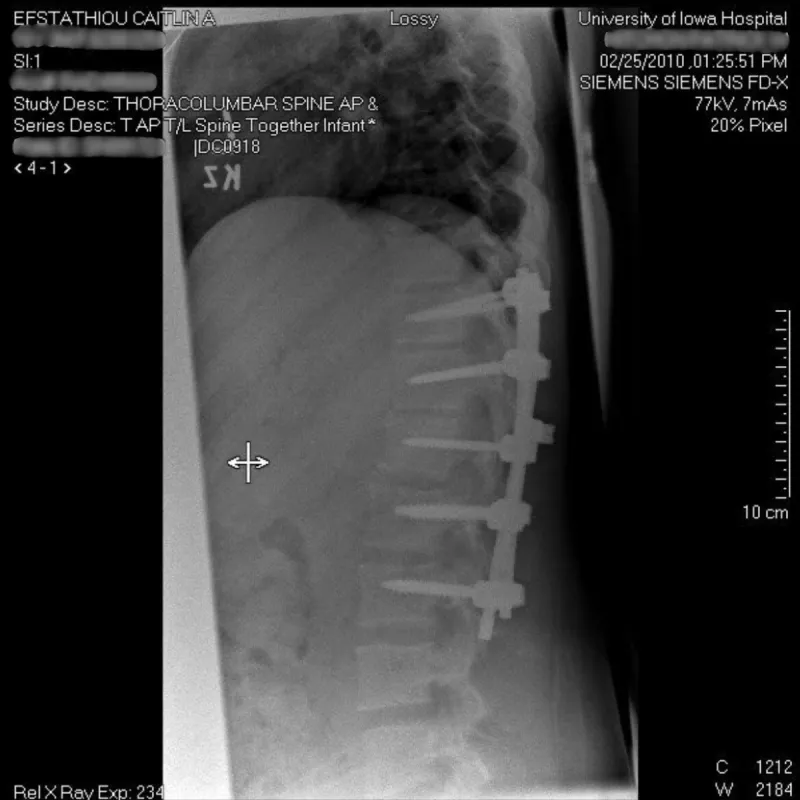

Efstathiou was transported to a Davenport hospital with internal bleeding, all her ribs broken, a lacerated liver, a broken leg, fractures in her hip socket, punctured lungs, a ruptured spleen, a broken back, and an arm with severe abrasions.

She spent four days undergoing surgeries and receiving care before her neurosurgeon determined the severity of the back injury required a referral to UI Health Care. She spent a month recovering in Iowa City.